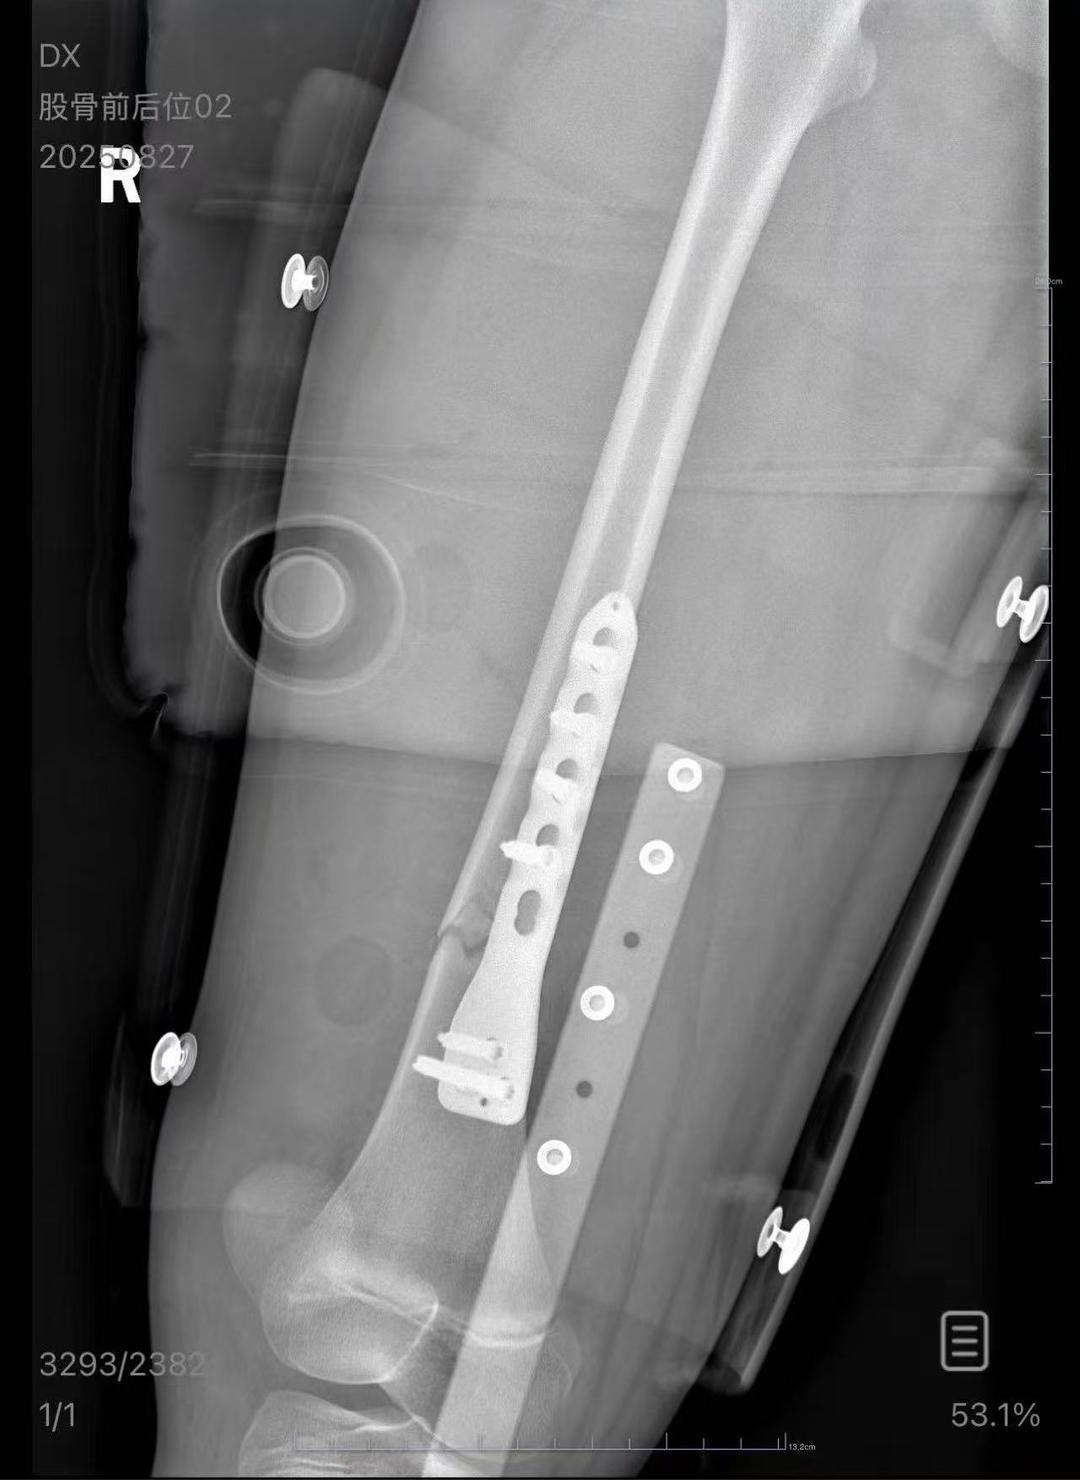

朱女士向记者出示的医院病历显示,8月24日凌晨,朱女士的女儿到医院就诊。医院诊断朱女士的女儿右股骨骨折,需要住院进一步治疗。

▲朱女士女儿手术后拍的X光片 受访者供图